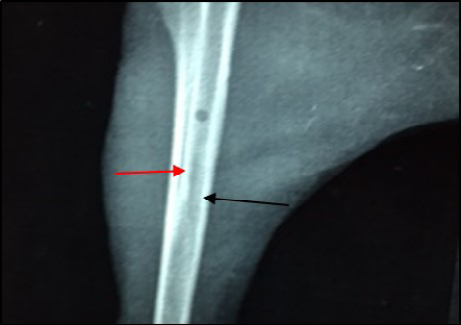

Site of operation, 14 days post treatment with Ceftaroline given intramuscularly (Group D). Still the medullary canal is not clear. Thickened cortex (→) and Endosteal reaction appeared clearly (→) (ML View)